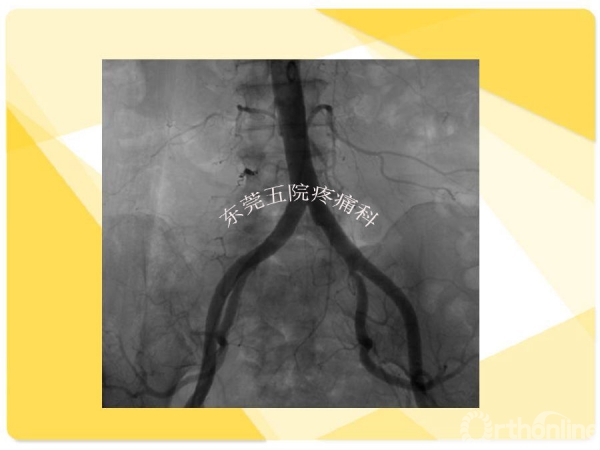

如何在椎间孔镜术前有效预防并发症的发生?如果不幸发生了该如何快速准确地处理?广东省东莞市第五人民医院疼痛科康健主任医师为大家分享了他的经验——